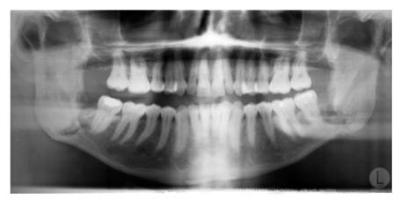

X-ray of Teeth

© 2009 Nucleus Medical Media, Inc.